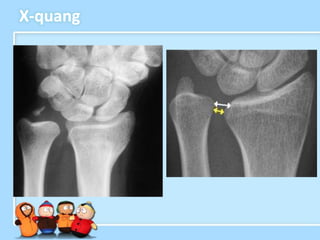

Chẩn đoán hình ảnh – X-quang

• Tư thế là chìa khóa để chụp được một phim

cổ tay tốt

• Gãy nền mỏm trâm

• Gãy đốm nhỏ từ hố

tam giác

• Giãn rộng DRUJ

• Khoảng chênh quay

trụ âm > 5 mm so với

cổ tay đối bên

• Nakamura và cs

– khoảng cách thuyền đậu (giữa bờ trước

của xương thuyền và xương đậu) < 3mm

– khoảng cách quay trụ (khoảng cách giữa

bờ sau của xương quay và xương trụ) >

5 mm